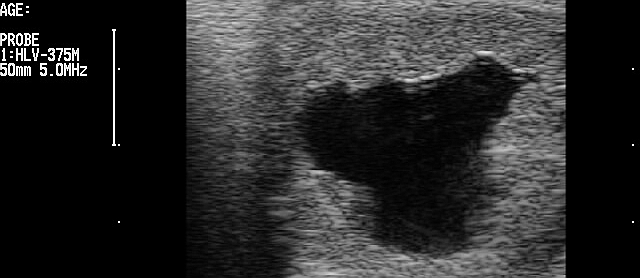

13 days old embryo

15 days old embryo